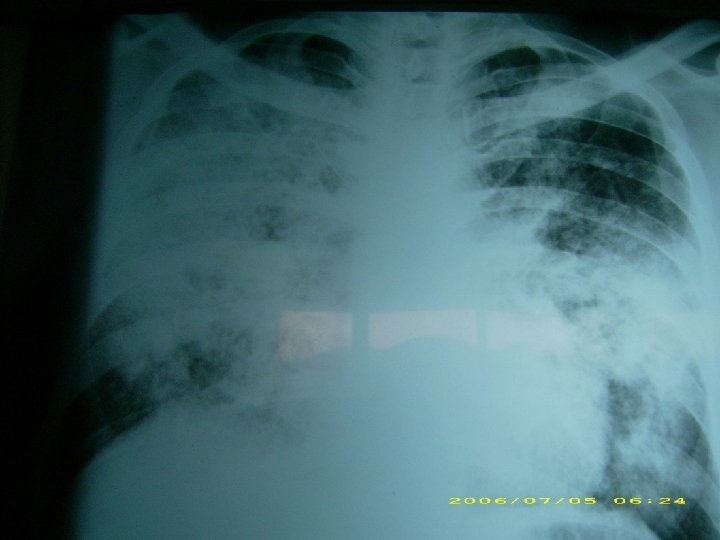

NEUMONIA AGUDA Caracteristicas clínico-radiológicas o Etiología bacteriana: consolidación lobar, cavitación y derrame pleural. o Compromiso difuso bilateral: etiología viral, neumonía atípica y por pneumocystis carinii. o Staphylococus aureus: de focos múltiples, neumatoceles. o Legionella: de focos múltiples, progresión radiológica rápida. o Necrotizante, con abscesos o empiema: por gramnegativos, estafilococo, por anaerobios.